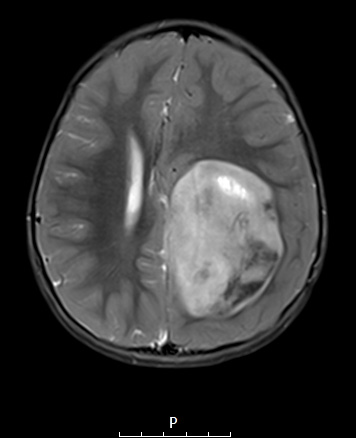

Washington University Experience | NEOPLASMS (EMBRYONAL) | ETMR - Embryonal Tumor Multilayered Rosettes | 8A3 ETMR (Case 8) T2W 1 - Copy

8A3,4 The image is patchy hyperintense in this T2-weighted image as seen in axial and sagittal scans.